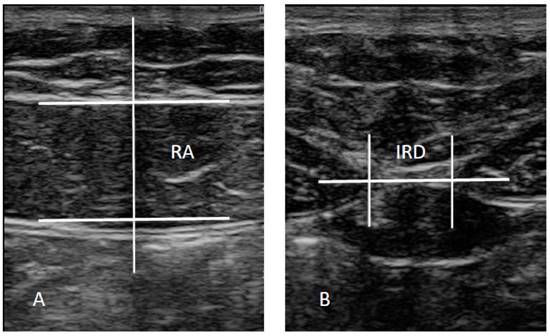

The ultrasound imaging assessment was carried out using a LogiQ P7 ultrasound system (GE Healthcare; UK) with a 4 to 13 linear transducer (L6- 12- RS type; 38-mm footprint). Ultrasound assessments of the RA, ipsilateral to the AT, and IRD were carried out in the supine position, with the transducer aligned with the umbilicus for the RA examination (Figure 2A) and just under the umbilicus for the IRD measurement (Figure 2B) in accordance with Whittaker et al. [27], who reported excellent interday and interexaminer reliability (intraclass correlation coefficients from 0.92 to 0.99) for these ultrasound measurements. Assessments were carried out prior to any intervention, and at 4 and at 12 weeks post-intervention, both with calf muscles at rest and in maximal isometric contraction. The mean of 3 repeated values was collected for each measurement with the transducer at the same point at the end of the expiration. Muscle thickness was described as the distance inside the caliper lines of each muscle (Figure 2A) and IRD was consider as the distance between the RA muscles (Figure 2B) [27]. ImageJ software (version 2.0) was used to analyze the images offline.

Figure 2

Ultrasound assessments. Abbreviations: IRD, inter-rectus distance; RA, rectus anterior.